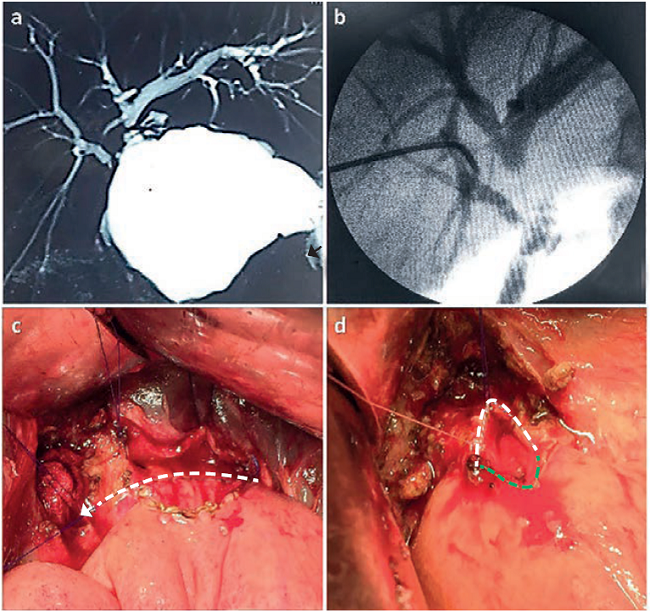

Se diagnosticó una lesión quirúrgica de la vía biliar (de tipo IV, según la clasificación de Bismuth) y un bilioma subhepático (figura 1a). La colección subhepática se drenó por vía percutánea con guía por ultrasonido; después de ocho semanas, tiempo en que mejoraron sus condiciones clínicas, se llevó a cabo el protocolo de estudio preoperatorio, el cual incluyó: colangiografía a través del tubo de drenaje subhepático, colangiorresonancia magnética y angiotomografía hepática.

La doble anastomosis hepático-yeyuno en Y de Roux se llevó a cabo según la técnica que se describe a continuación. Previa exposición y disección de la placa hiliar, se comprobó la ubicación y la separación entre ambos conductos hepáticos (derecho e izquierdo) mediante colangiografía intraoperatoria (figura 1b). Se incidió el conducto hepático izquierdo en su cara anterior y se logró una apertura amplia. Se resecó el segmento 4b del hígado, y se procedió a la exposición y apertura longitudinal del conducto hepático derecho. Se practicó la doble anastomosis hepático-yeyuno en Y de Roux, con material sintético, monofilamento 5-0 (figura 1, c y d); ambas anastomosis se iniciaron en su cara posterior. Se dejó drenaje abdominal y un catéter transparieto-hepático por encima de la anastomosis bilioentérica derecha, para hacer el control radiológico.

Un punto interesante por analizar en relación con la anatomía biliar de la paciente descrita, es que, en los estudios preoperatorios, lo identificado como conducto hepático derecho (figura 1) pudiera haber sido interpretado como un conducto sectorial posterior derecho de amplio diámetro y, el conducto izquierdo, como la unión del sectorial anterior derecho y el hepático izquierdo, lo cual se descartó durante la intervención quirúrgica, corroborándose una lesión de tipo Bismuth IV.

Ciertos detalles técnicos se asocian con un mejor resultado posoperatorio, según lo descrito por varios autores 1,17,18, a saber: hacer una anastomosis amplia mediante la apertura de la luz de ambos conductos hepáticos (figura 1, c y d), en tejido sano, para lo cual debe resecarse el tejido fibroso perianastomótico, sin tensión, con adecuada irrigación de ambos componentes (biliar e intestinal), y uso de material de sutura adecuado, idealmente, monofilamento reabsorbible 5-0.

Asimismo, y de ser necesario, debe llevarse a cabo la resección de tejido hepático (segmentos 4 o 5) para lograr una mayor superficie de exposición del conducto hepático derecho, sin disección excesiva de los conductos hepáticos, a fin de evitar la pérdida de irrigación sanguínea 19.